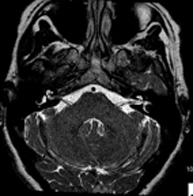

Prueba diagnóstica no invasiva que consiste en la obtención de imágenes de alta definición anatómica del cerebro mediante el empleo de un campo electromagnético y ondas de radio (con un emisor y un receptor). No utiliza radiación ionizante. Indicaciones: problemas vasculares, pérdida de memoria, epilepsia, cefalea, malformaciones, sospecha de tumor, meningitis. - RM Cais